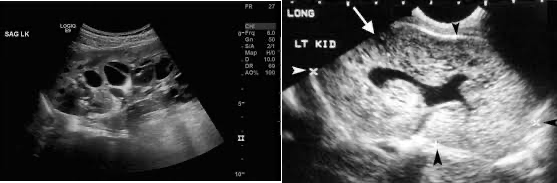

다낭 신질환 (polycystic kidney disease)

좌: ADPKD. multiple large cyst 및 enlarged kidney

우: ARPKD. Enlarged kidney with multiple small hyperechoic foci (small cysts)

• 상염색체 우성 다낭신병 (ADPKD)

• 상염색체 열성 다낭신병 (ARPKD)